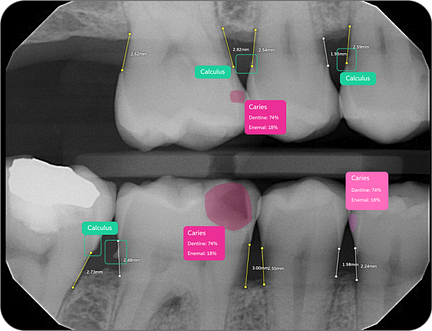

43% of caries go undiagnosed

20% of diagnosed caries aren't actually decay

Pearl's Second Opinion AI system has demonstrated remarkable efficacy, with Ophir Tanz noting, "We pick up on average 37% more disease per radiograph encountered." This capability enables earlier intervention and more preventative care approaches.